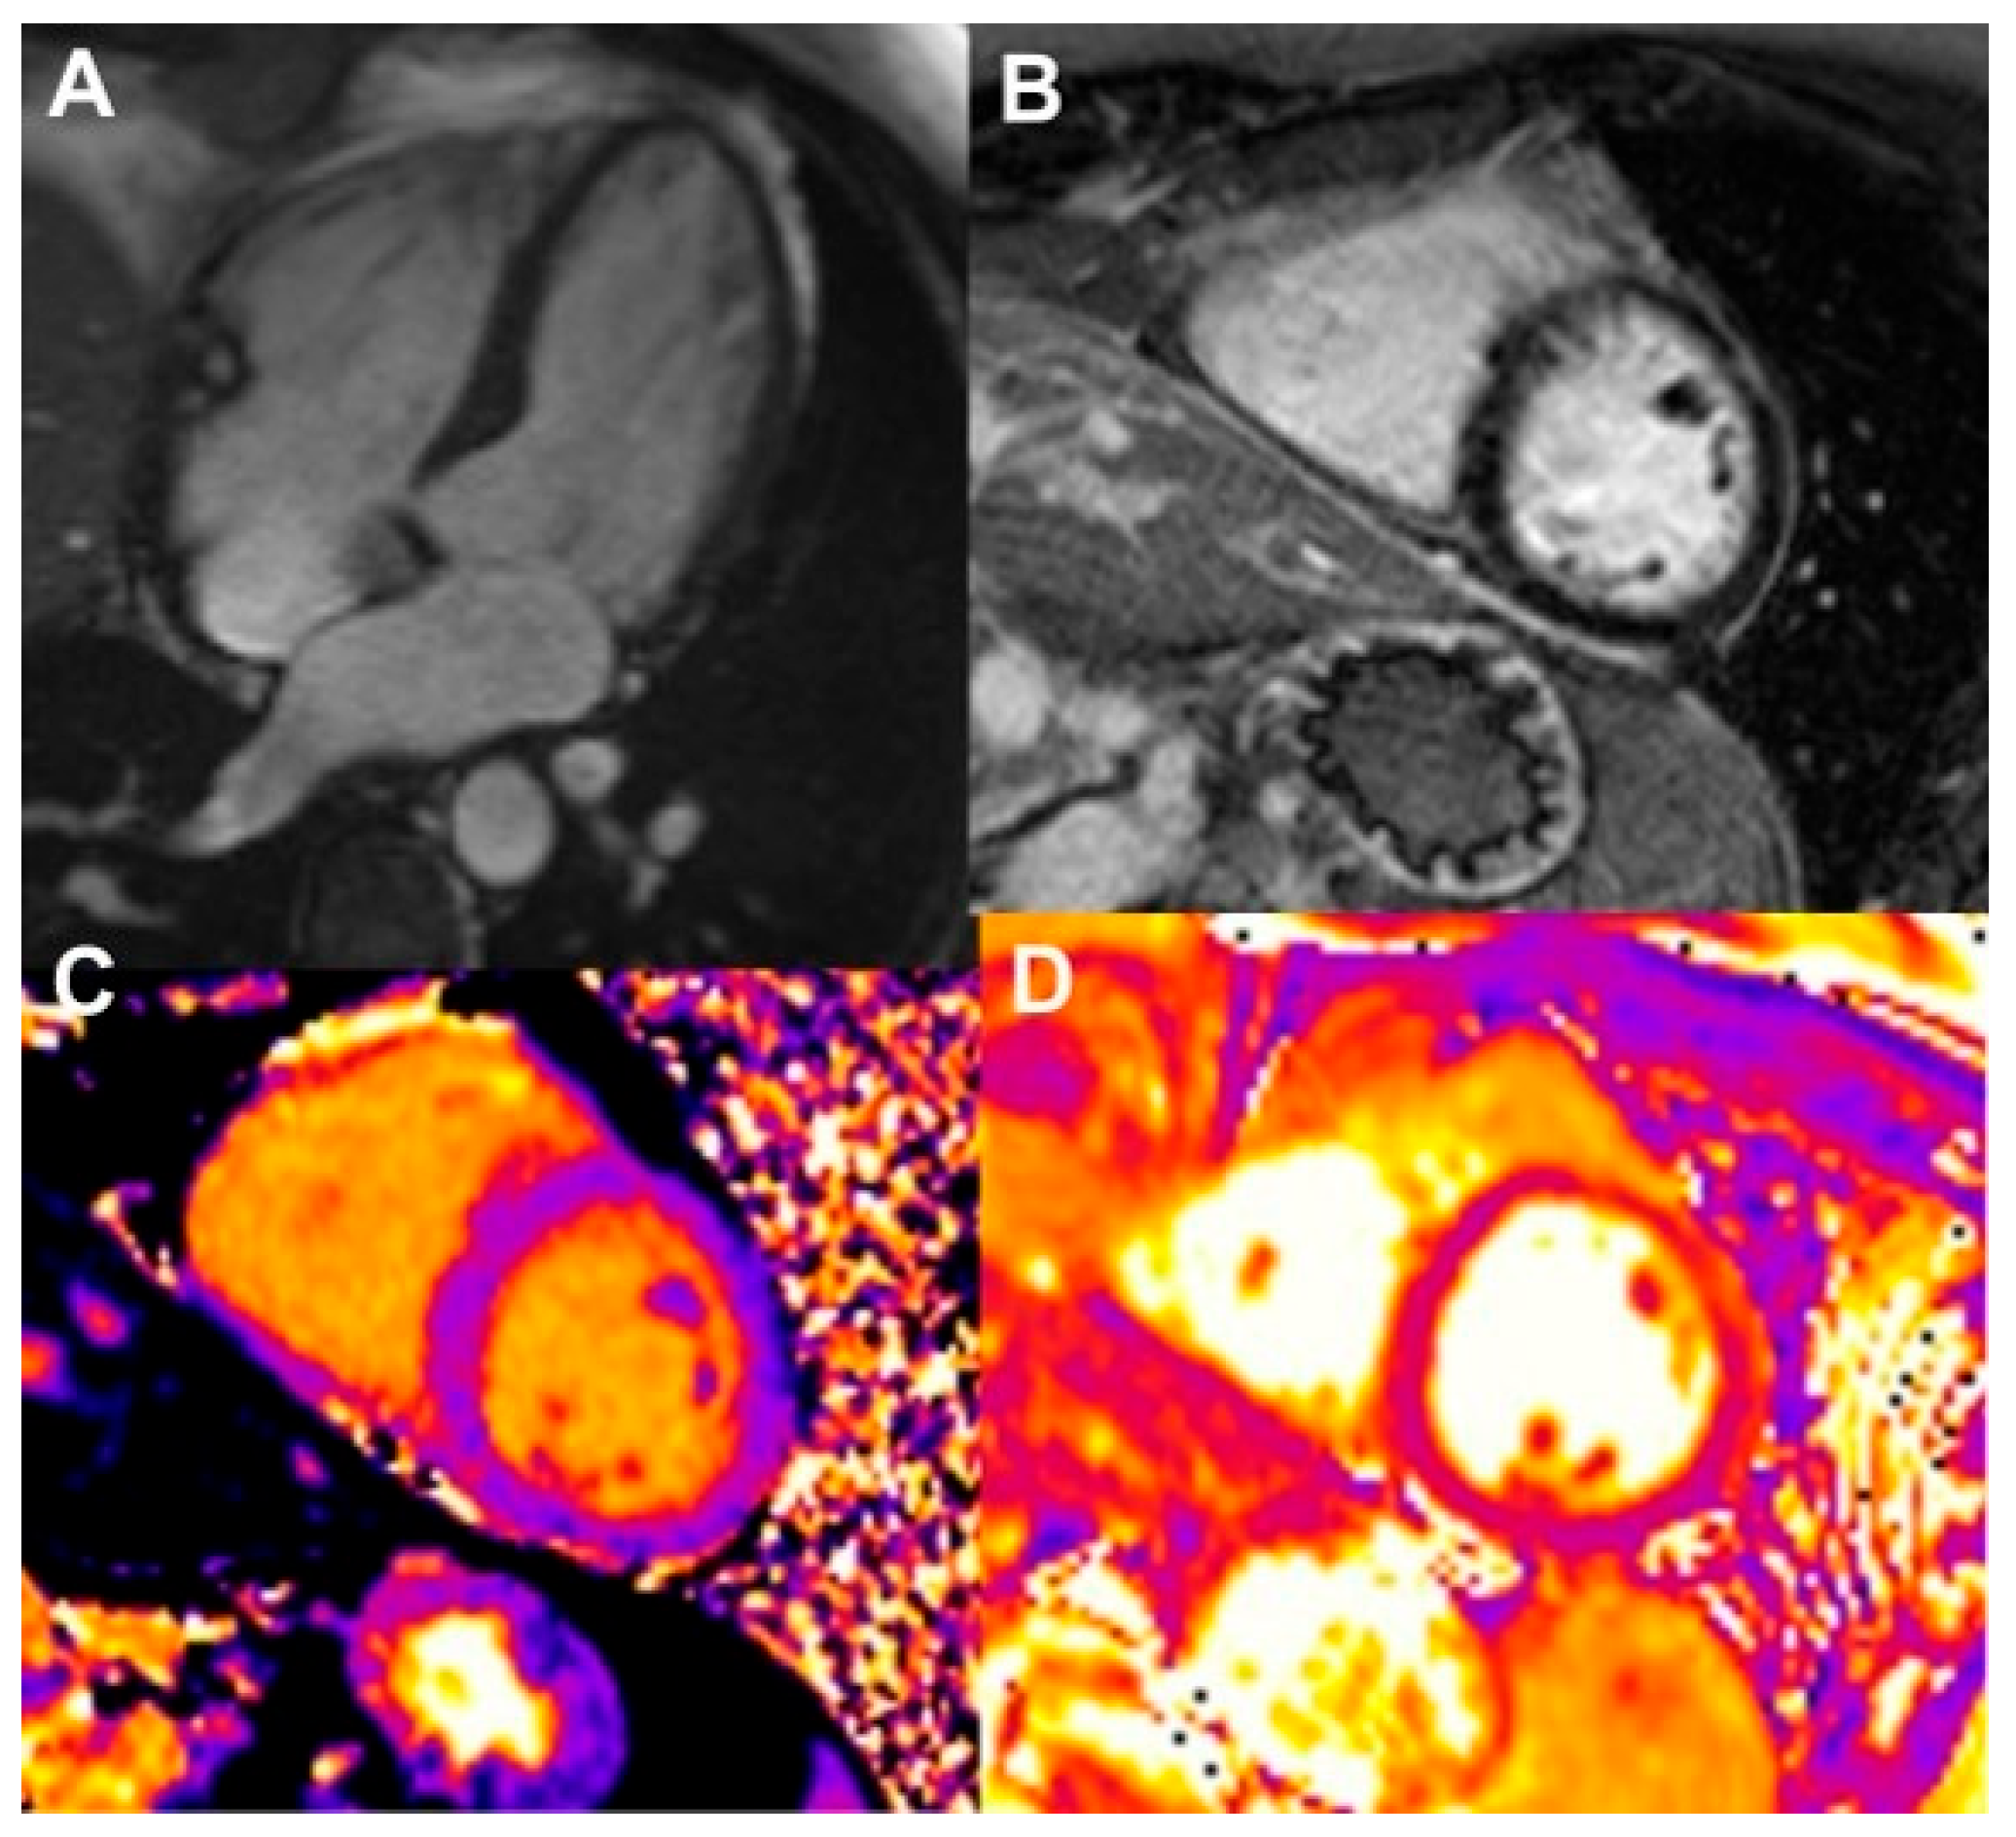

Myocarditis

Pericardial Disease

- Ferreira, V.M.; Schulz-Menger, J.; Holmvang, G.; Kramer, C.M.; Carbone, I.; Sechtem, U.; Kindermann, I.; Gutberlet, M.; Cooper, L.T.; Liu, P.; et al. Cardiovascular Magnetic Resonance in Nonischemic Myocardial Inflammation. J. Am. Coll. Cardiol. 2018, 72, 3158–3176. [Google Scholar] [CrossRef]

- Burrage, M.K.; Ferreira, V.M. The Use of Cardiovascular Magnetic Resonance as an Early Non-Invasive Biomarker for Cardiotoxicity in Cardio-Oncology. Cardiovasc. Diagn. Ther. 2020, 10, 610–624. [Google Scholar] [CrossRef]

- Bogaert, J.; Francone, M. Pericardial Disease: Value of CT and MR Imaging. Radiology 2013, 267, 340–356. [Google Scholar] [CrossRef]